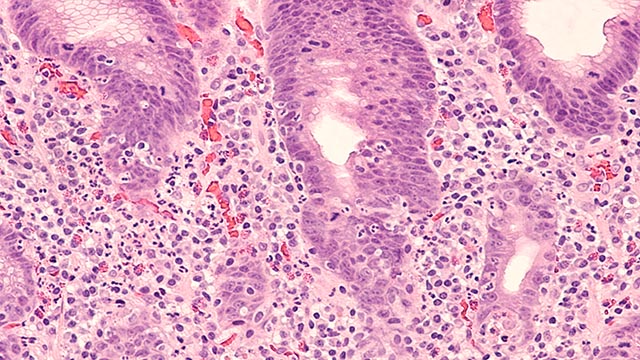

Pozdravujem, pán Planieta, toto je môj príbeh: Som YANGový KOV so zdravotnými predispozíciami na oslabené pľúca a hrubé črevo (na konzultácií sme sa bavili aj